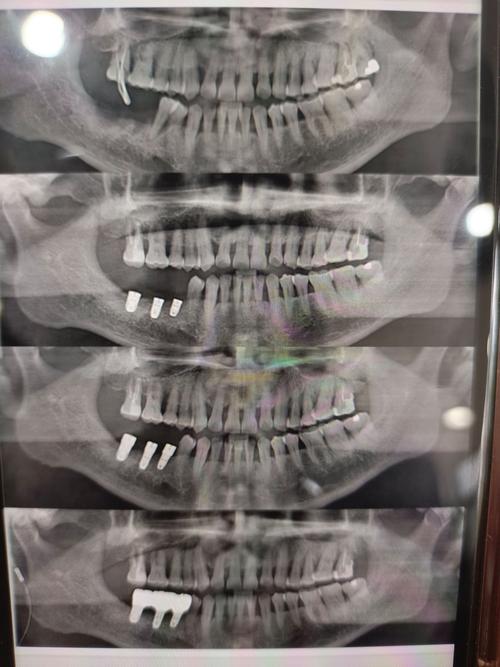

- 图像后处理:医生需通过专业软件(如Dexis、OnDemand)进行三维重建,多平面观察(MPR、CPR)、测量骨量、模拟种植体植入路径,确保方案可行性。